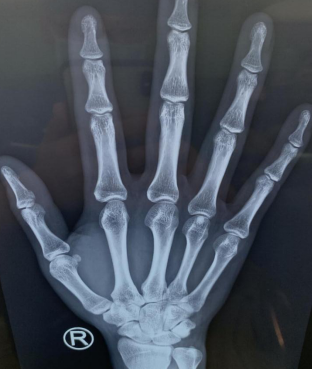

两天后,刘某感觉右手拇指疼痛加重、活动受限,于是来到betway在线登陆。手外科四病区收治后,拍片检查看不出来鱼刺具体位置,只能根据刘某的描述,拆除右手伤口缝线,延长伤口,在大概2厘米的位置终于找到了鱼刺,原来鱼刺藏在了桡腕关节囊内。

术前CT

取出鱼刺(左图)鱼刺约1cm(右图)